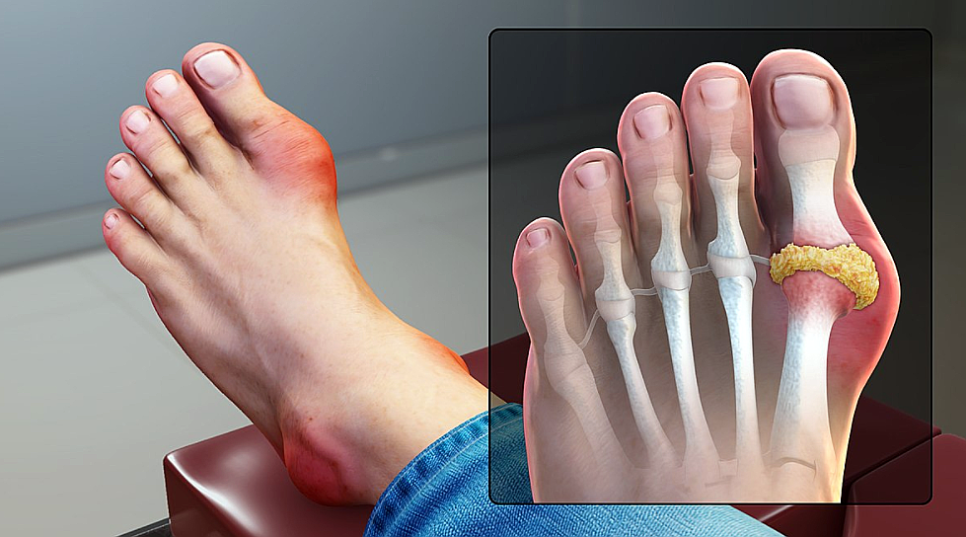

통풍을 옛날에는 ‘귀족병’이라고 했습니다. 기름진 음식과 술을 많이 마실 수 있는 상류층 사람들이 주로 걸렸기 때문입니다. 하지만 지금은 누구나 걸리고 점점 나이도 어린데서도 발생한다고 합니다.

바람은 푸린이라고 하는 단백질의 대사 이상으로 많아진 요산이 체내에 축적되어 관절과 조직에 침착하게 일어나는 병입니다. 따라서 체내에 요산이 과도하게 축적되지 않도록 푸딩이 많이 함유된 음식을 줄이고, 체내의 요산이 잘 배출되도록 해야 합니다.

통풍이 우려되는 경우 1. 적정 체중유지 비만은 다른 요인보다 통풍과 직접적인 관련이 있는 것으로 알려져 있습니다. 비만은 고요산혈증을 유발하고 과도한 체중은 관절에 부담을 줍니다. 관절에 높은 압력이 가해지면 세포가 파괴되고, 이 과정에서 요산이 생성되기 때문에 통풍 발작이 일어나는데 좋은 조건입니다.

요산 혈증의 경우 비만에 앞서 나타날 수도 있는 것입니다만. 고요산 혈증이 비만과 통풍을 동시에 유발할 수도 있다고 하는 것이군요. 통풍의 절반 이상이 과체중으로 발생하고, 실제로 통풍 환자의 60%가 비만이라는 데이터도 있군요.